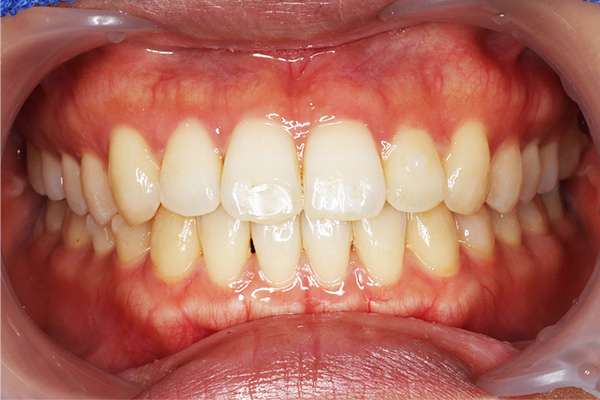

咬合再構成も含めた審美的な補綴治療を学べます。